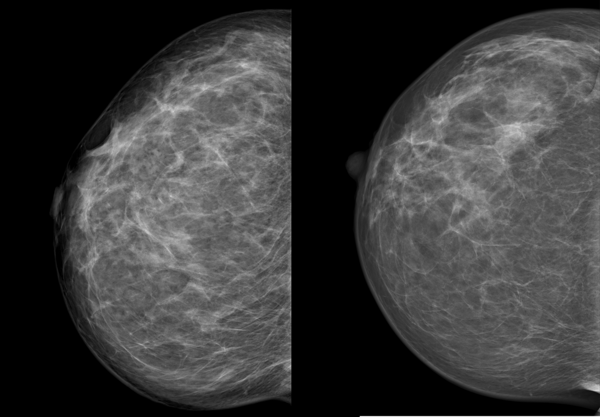

Die Kompression beeinflusst die Qualität der Aufnahme. Je dünner die Brust ausgestrichen ist, desto besser und klarer wird das Bild, wie das Beispiel unten zeigt.

Wir sehen dieselbe Brust im Abstand von zwei Jahren, die linke Aufnahme ist die neuere. Links erscheint die Brust wesentlich dichter, das Drüsen- und Bindegewebe ist unscharf, die Haut um die Brustwarze ist nur unzureichend abgebildet. Verdächtige Veränderungen könnten eventuell durch die schlechte Bildqualität überdeckt werden. Die Frau hatte an diesem Tag eine sehr druckempfindliche Brust, weshalb keine stärkere Kompression möglich war.